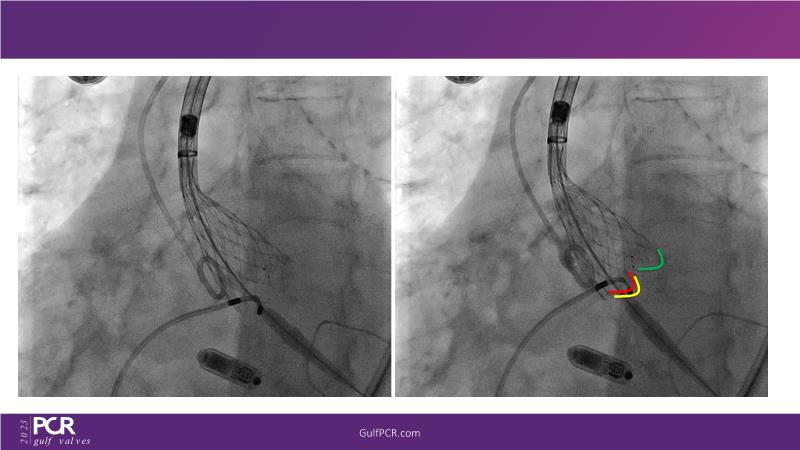

The primary focus of this GulfPCR-GIM 2023 session revolves around pre-procedural planning considerations, valve selection, and managing complex anatomies using both traditional self-expanding valves and the Evolut FX system. Additionally, the session aims to explore the work-up protocol for patients grappling with severe AS and advanced CKD, elucidate the algorithm for selecting the appropriate TAVR platform, discuss strategies to reduce contrast utilization, and highlight the distinctive advantages offered by the Evolut FX system.

• To learn more about optimization of valve deployment